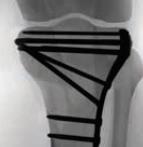

Proximal Tibia Fracture System

• The Proximal Tibia Fracture System is a comprehensive plating set designed for treatment of a variety of tibial plateau fractures.

• The system features three styles of Lateral Proximal Tibia Plates, a Medial Locking Plate, and a Posteromedial Buttress Plate to address intra-articular and extra-articular fractures of the proximal tibia.